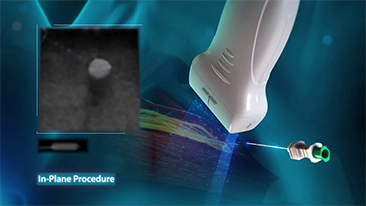

L'imagerie de contraste joue un r?le important en cas de lĂŠsions hĂŠpatiques focales, par exemple hĂŠmangiome ou cancer hĂŠpatique. La technologie d'imagerie de contraste UWN+ ultra-large et non linĂŠaire offre une meilleure pĂŠnĂŠtration, un rapport contraste-tissu plus ĂŠlevĂŠ, avec un index mĂŠcanique (IM) plus faible et une observation plus longue du temps de perfusion.